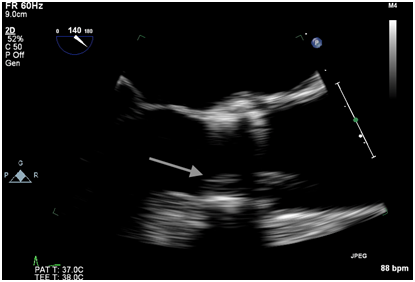

Figure 1B Intraoperative TEE post valve deployment showing an echodensity attached to the ventricular side of the strut along the right coronary cusp protruding into the left ventricular outflow tract.

Immediately after the prosthetic valve deployment, intraprocedural TEE revealed a 20 x 9.5 mm mobile echo density attached to the ventricular side of the strut along the right coronary cusp. The structure intermittently prolapsed through the leaflets of the newly placed valve prosthesis during systole (Figure 1A, 1B). However, only mild (1+) central aortic regurgitation was noted (Figure 2). There was no left ventricular outflow tract obstruction and the prosthetic valve leaflet excursion was otherwise normal. The peak and mean aortic valve gradients were 7 and 4 mm Hg respectively post deployment.